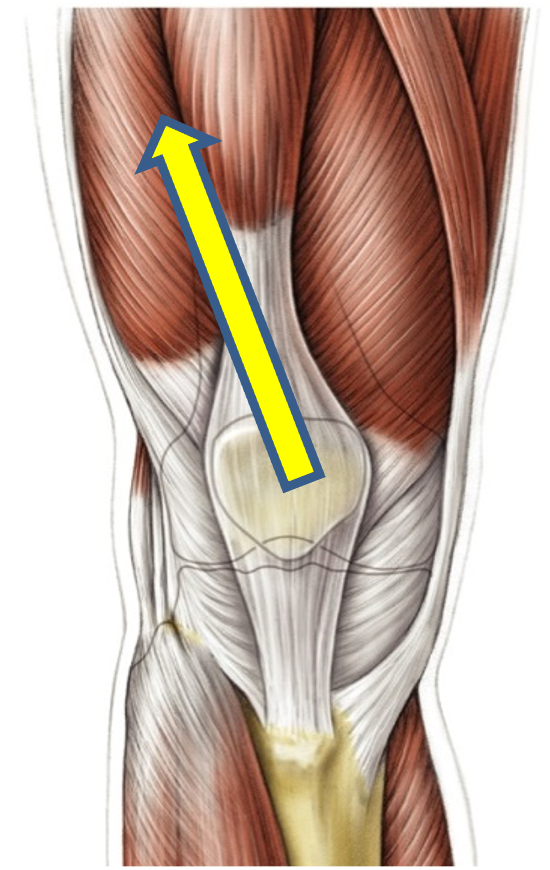

What is this ?

What causes it ?

Patella dislocation

Cause:

The alignment of the femoral and tibial shafts is such that the quadriceps pulls the patella superiorly and laterally

Increase risk with females

Knee effusion increases the risk of patella dislocation because vastus medialis quickly wastes.

What prevents a knee dislocation occuring ?

Prominent lateral part of the trochlea groove

Vastus medialis (MOST IMPORTANT)